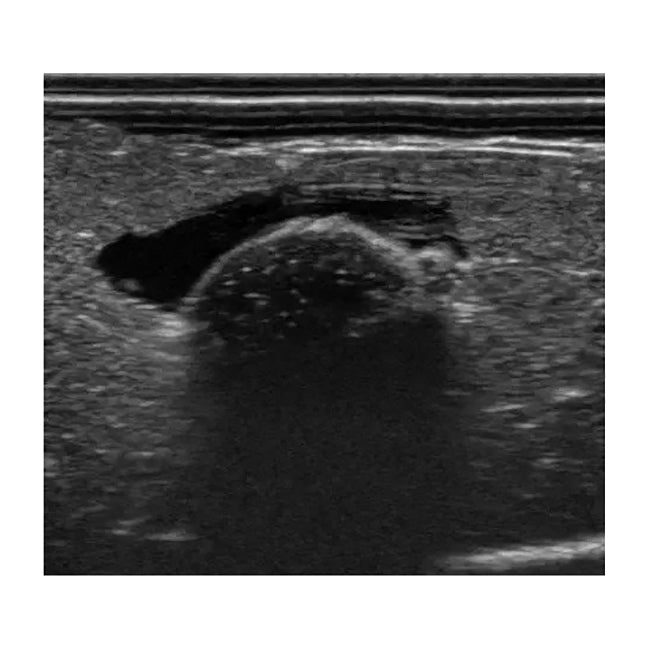

MW63 Pressure Sores Simulator is a decubitus care skills trainer for the new era. Its detailed representation allows for a wide range of training scenarios, including sore assessment , ultrasound assessment of deep tissue injury, and necrotic tissue removal.

• Assessment of deep tissue by ultrasound

• Ultrasound

• Sciatic pressure sore (3 types including deep tissue injury)

• 2 types of echo pads

11446-070echo pads set (normal/edema)